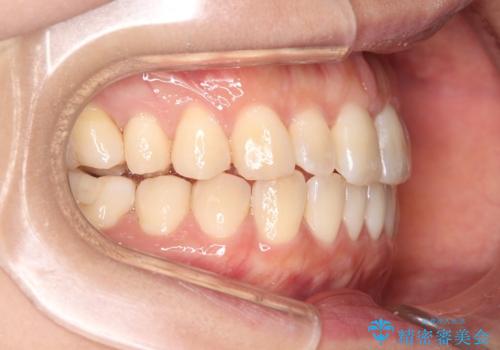

【インビザライン】前歯の捻れ気になる

- 上の前歯の捻れを主訴に来院されました。

前歯の捻れとがたつきを改善するために、IPR(歯と歯の間を削る処置)と歯列拡大をすることで歯並びを整えていく治療計画を立てました。

かみ合わせを整えるためにゴム掛けも行いながら、治療していきました。

患者様にマウスピースの使用とゴム掛けを頑張っていただいたおかげでリファイメント(マウスピースの再発注)も1回で終了することができました。